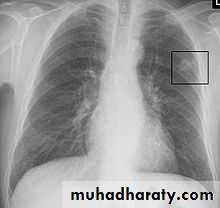

• A-Asymptomatic• Any smooth homogenous opacity of uniform density with clear cut border and little or no reaction around it on a chest X-Ray is a hydatid cyst unless proved the other wise .

• Radiological Findings

• 1-Smooth homogenous opacity (Intact H.C).• 2-Partial rupture (peri-vesicular pneumocyst).